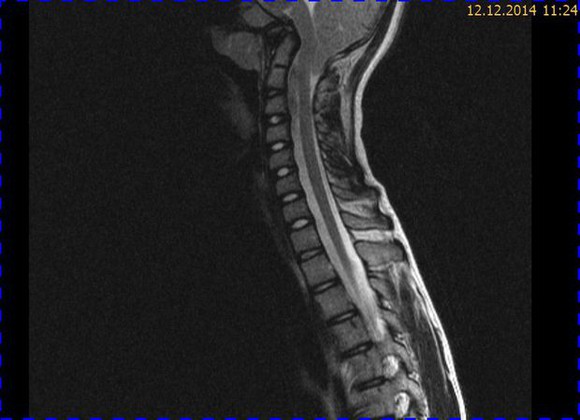

Abb. 1.2 Sagittales MRT (T2 TSE, 1 T): Streckfehlhaltung der HWS und oberen BWS, kein Frakturhinweis oder posttraumatische Myelopathie; die Kleinhirntonsillen reichen bis in das Foramen magnum

Abb. 1.3 Sagittales MRT (T2 TIRM): kein Hinweis auf mikrotrabekuläre Frakturen, regelrecht hydrierte Bandscheiben; die Kleinhirntonsillen lassen sich schlechter abgrenzen

Das Fallbeispiel 1 zeigt im Verlauf eine Komplikation bei einer Arnold-Chiari-Malformation Typ 1 bei einem zum Zeitpunkt der Erstdiagnose 12-jährigen Jungen. Dieser hatte im Sportunterricht einen schweren Medizinball geköpft und ein Stauchungs-trauma der Halswirbelsäule erlitten. Nach anfänglich symptomatischer frustraner Therapie wurde er vom behandelnden Orthopäden zur MRT der HWS überwiesen. Es wurde eine Streckfehlhaltung und flachbogig rechtskonvexe Skoliose diagnostiziert, klinisch bestand ein Torticollis. Eine knöcherne oder ligamentäre Verletzung wie auch eine Schädigung des Rückenmarks bzw. eine intraspinale Bandscheibendislokation konnten bildmorphologisch ausgeschlossen werden.

Trotz weiterer Schmerz- und Physiotherapie konnte keine Beschwerdereduktion erreicht werden. 2 Monate später erfolgte eine MRT des Kopfes zum Ausschluss einer posttraumatischen Veränderung.

Bei dieser Untersuchung wurde übersehen, dass die Kleinhirntonsillen in das Foramen magnum disloziert waren und eine Arnold-Chiari-Malformation mit Erweiterung des 4. Ventrikels und des Aquäduktes inklusive Kleinhirntonsillentiefstand vorlag. Bei zwischenzeitlich auswärtig erfolgtem CT der HWS wurde eine Anlagestörung im kraniozervikalen Übergang beschrieben. Eine Kontrolluntersuchung des Kopfes weitere 4 Monate später dokumentierte neben einem medullären Ödem einen progredienten Tonsillentiefstand, der zur neurochirurgischen Behandlung mit operativer Erweiterung des Foramen magnum führte.